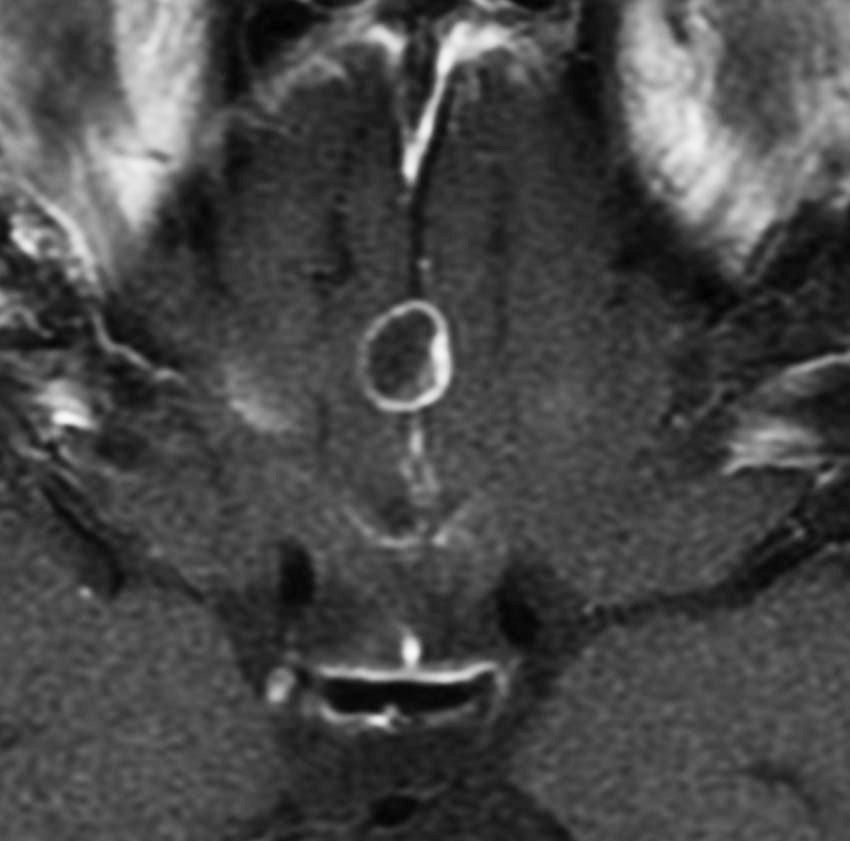

第3脳室内のadamantinomatous craniopharyngiomaです。これを両側前頭開頭,経脳梁法 transcallosall approachで摘出しました。下垂体と下垂体柄を温存するためです。

初回手術から6年後,原発部位に腫瘍はありません。しかし,前頭部大脳鎌(赤矢印)に腫瘍が発生しました。これは手術経路(緑の線)に沿った位置にあるので,drop metastasisだとわかりました。病理は初回と同じものです。このdrop metastasisは意外に多いものです。頭蓋咽頭腫は,極小の腫瘍片でも脳表や脳槽にこぼれ落ちれば,そこで着床して,数年後に再発となって現れるということを示しています。ですから,手術の時に断片を残したり落としたりしてはなりません。